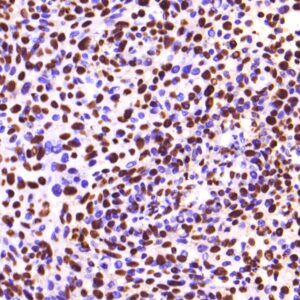

BioGenex offers fluorescein-labeled oligonucleotide probes to detect DNA or RNA using In situ Hybridization (ISH). These probes allow quantitative detection of specific DNA/RNA sequences in their native form within the cells of formalin-fixed paraffin-embedded (FFPE) tissue sections. These probes offer reliable, highly sensitive, and easy-to-perform DNA and RNA ISH assays when used with the BioGenex ISH Detection Systems.